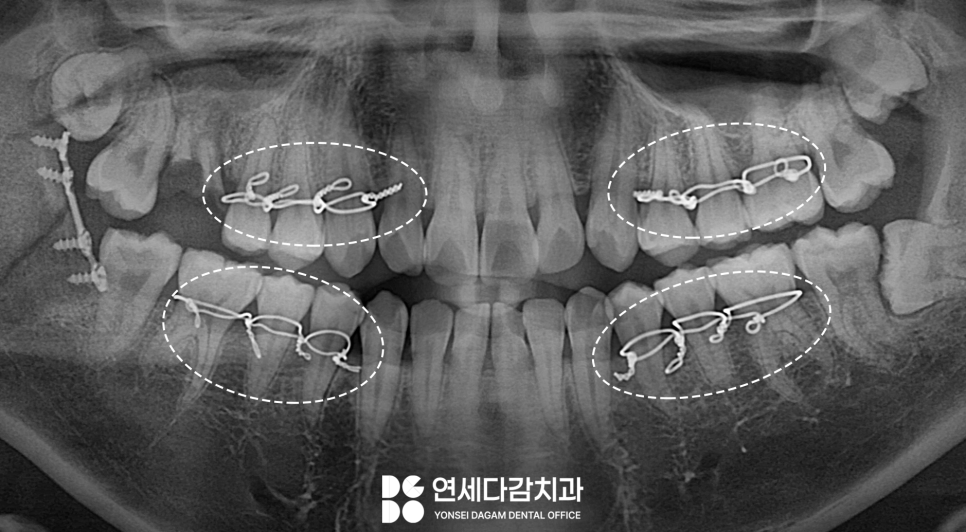

골절 수술 후 상하악 치아에

티타늄 플레이트와

나사를 이용하여 고정합니다.

이 과정에서 교합 관계의 정확한

복원을 중요시 하게 됩니다.

과거에는 턱뼈에 직접 와이어를

감는 방법을 사용했지만,

현재는 치아를 이용한 방법이

일반적입니다.

치아가 충분히 있고 건전한 경우

이 방법으로 적용됩니다.